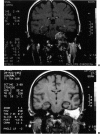

Posterior fossa meningioma is the second most common tumor in the cerebellopontine angle. It has a higher rate of postoperative morbidity and mortality compared to acoustic neuroma. Forty posterior fossa meningioma patients managed in our centers were reviewed. Thirty-nine patients were managed surgically with 42 surgical procedures. The approaches used were the translabyrinthine approach in 18 patients (43%), the modified transcochlear in 11 cases (26%), the petro-occipital transsigmoid in 5 cases (12%), the suboccipital in 4 cases (10%), the petro-occipital trassigmoid transcervical in 2 cases (5%), the petro-occipital transsigmoid transtentorial in 1 case (2%), and a subtemporal transtentorial for another case (2%). Facial nerve anatomical integrity was preserved in 87% of procedures but was interrupted in 5 cases, with 4 of the latter subsequently repaired. Total tumor removal was accomplished in 38 cases. A second-stage total tumor removal is planned for the remaining case. There was only one case of perioperative death and no cases of radiological recurrence so far.